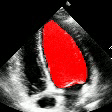

Echocardiography Video

Input Raw Echo Video

Segmentation Mask

Predicted Mask of Left Ventricle

Echo Video

Predicted LV Mask

ECG

Generated ECG Visualization

Fig. 8 — End-to-end demo: raw input → segmentation overlay → ECG waveform.